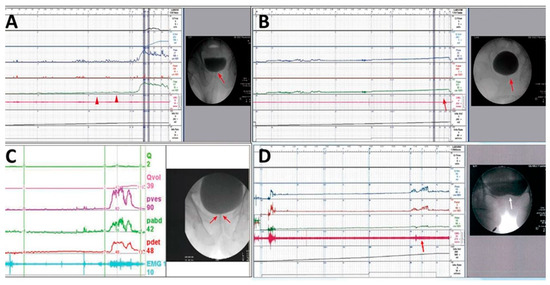

5.3. Baseline Evaluation and Diagnosis